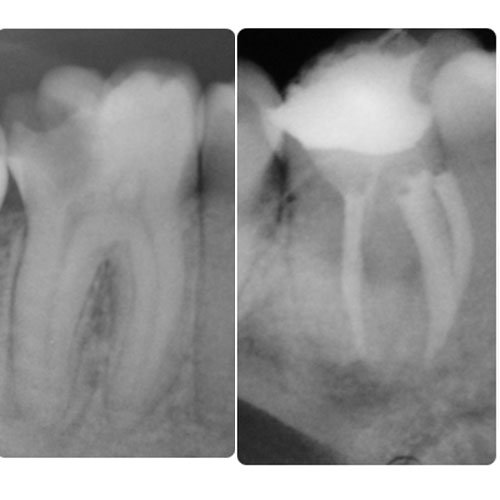

Conozca más casos dentales en nuestra Fanpage: ABC Clinica Dental dentista en guatemala. Implantes dentales